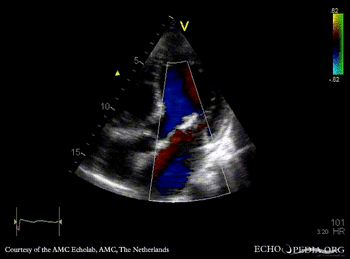

Endocarditis of mitral valve

A3CH: vegetations on AMVL A2CH

A5CH A5CH: Color doppler, severe mitral regurgitation